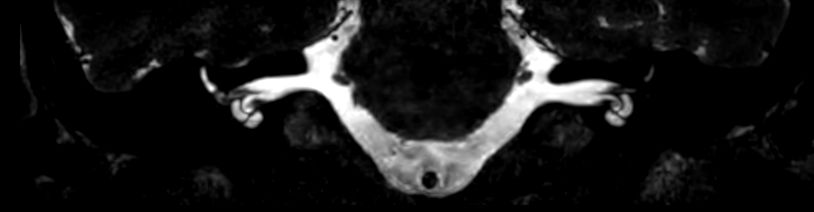

Axial 3D T2w TSE DRIVE

3D T2w TSE DRIVE (Coronal reformat)

Axial 3D T2w TSE DRIVE (volume rendering)